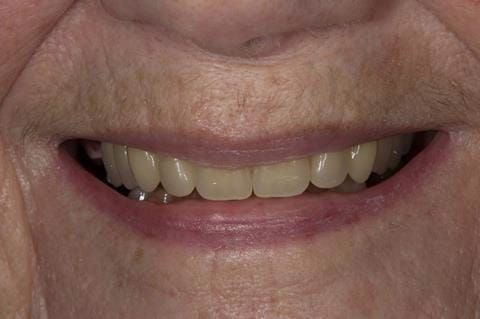

Following consultation and second discussion appointment the patient chose to have option 2 namely, a window denture - maxillary cobalt chromium based partial denture. The clinical situation and treatment process is shown in detail below with photographs. The patient was successfully rehabilitated with this and her quality of life considerably improved. The clinical work was provided by Finlay and the technical work by Rowan.